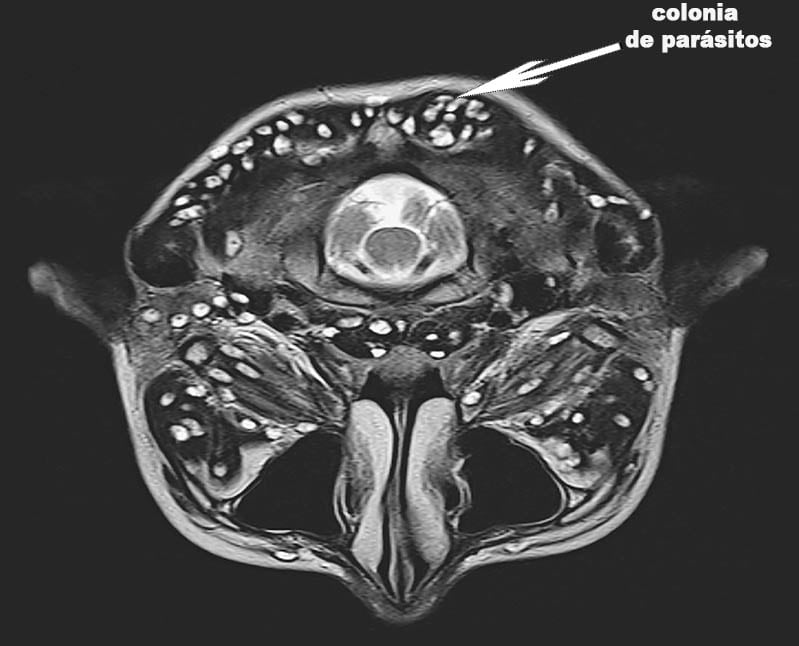

¿Sabes cuántas personas murieron por parásitos en ? El año pasado, 355.000 personas murieron en Colombia. De estos, 231.000 tenían sudoración excesiva. Esto es más de la mitad de todas las víctimas. Los parásitos ingresan al torrente sanguíneo y se diseminan por todo el cuerpo. Destruyen nuestro cuerpo desde el interior y afectan a todos los órganos. Las esporas pequeñas se adhieren a los órganos internos y se multiplican, provocando el desarrollo de patologías. En consecuencia, la infección también afecta a los órganos vitales. Esto significa que el cuerpo se está pudriendo de adentro hacia afuera. Con el tiempo, el corazón no se puede sostener, se rompe un vaso sanguíneo en el cerebro o se desarrolla CA en el hígado. Los riñones también pueden fallar. Cualquiera que sufra de parásitos tiene estos riesgos. El sistema inmunológico está debilitado por los frecuentes resfriados y el estrés completa el cuadro fatal.

Uno de los tipos de parásitos más comunes: